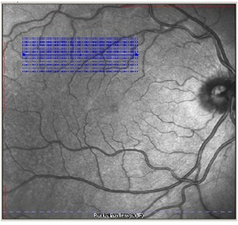

二、唯一具有Eye-Tracking实时主动动眼追踪技术的OCT——“所见即所得”Eye-Tracking动眼追踪技术可以消除扫描伪迹,避免检查出现漏诊和误诊,并具有*好的重复性

Eye-Tracking动眼追踪技术衍生出TruTrackTM技术,实现随诊时精确同一位置,为精确量化评价疾病进展和治疗效果变化提供了可能——PDT和抗VEGF治疗疗效评估金标准

五、唯一具有ART(Automatic Real Time)技术的OCT

基于Eye-Tracking技术保障下的ART(Automatic Real Time)降噪技术,有效降低图像噪点,大大提高图像分辨率 :

ART启动利于定位眼底,针对性的检查病变区域